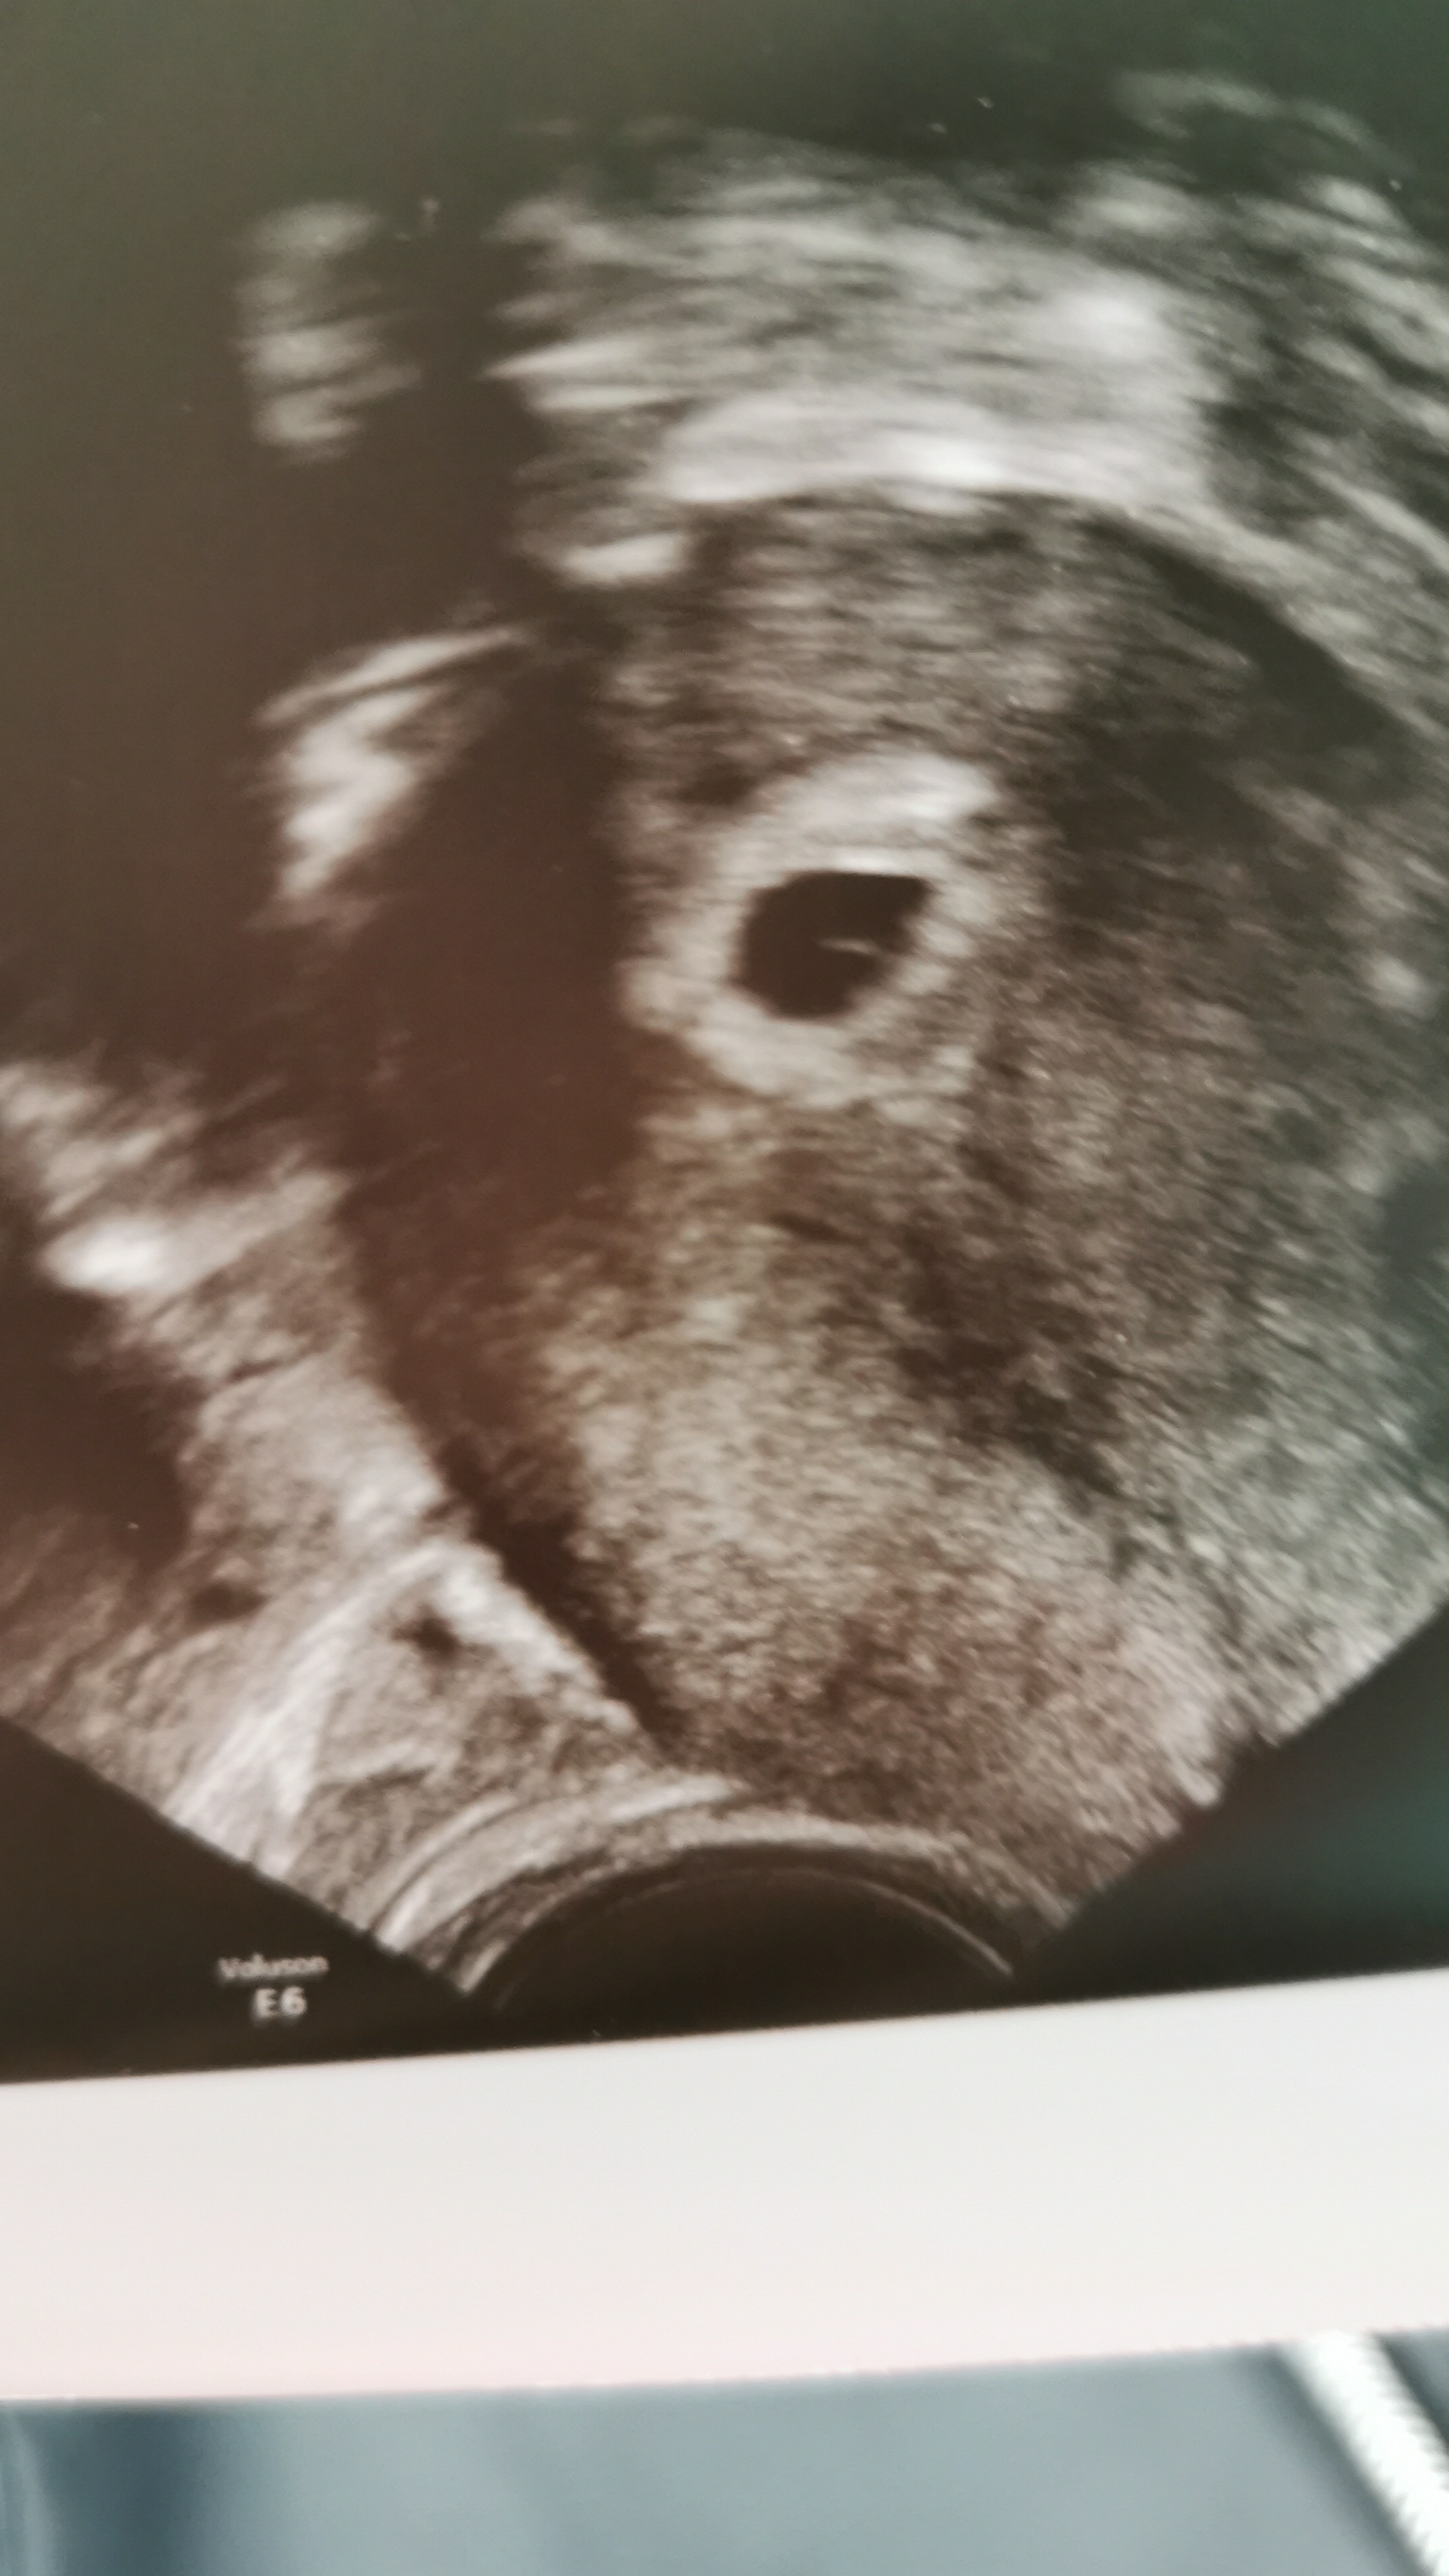

6 tydzień ❤️❤️❤️❤️

Załączniki

• IMG-545e140190a94db53b795b4abced6b87-V.jpg

IMG-545e140190a94db53b795b4abced6b87-V.jpg

912 KB · Wyświetleń: 103